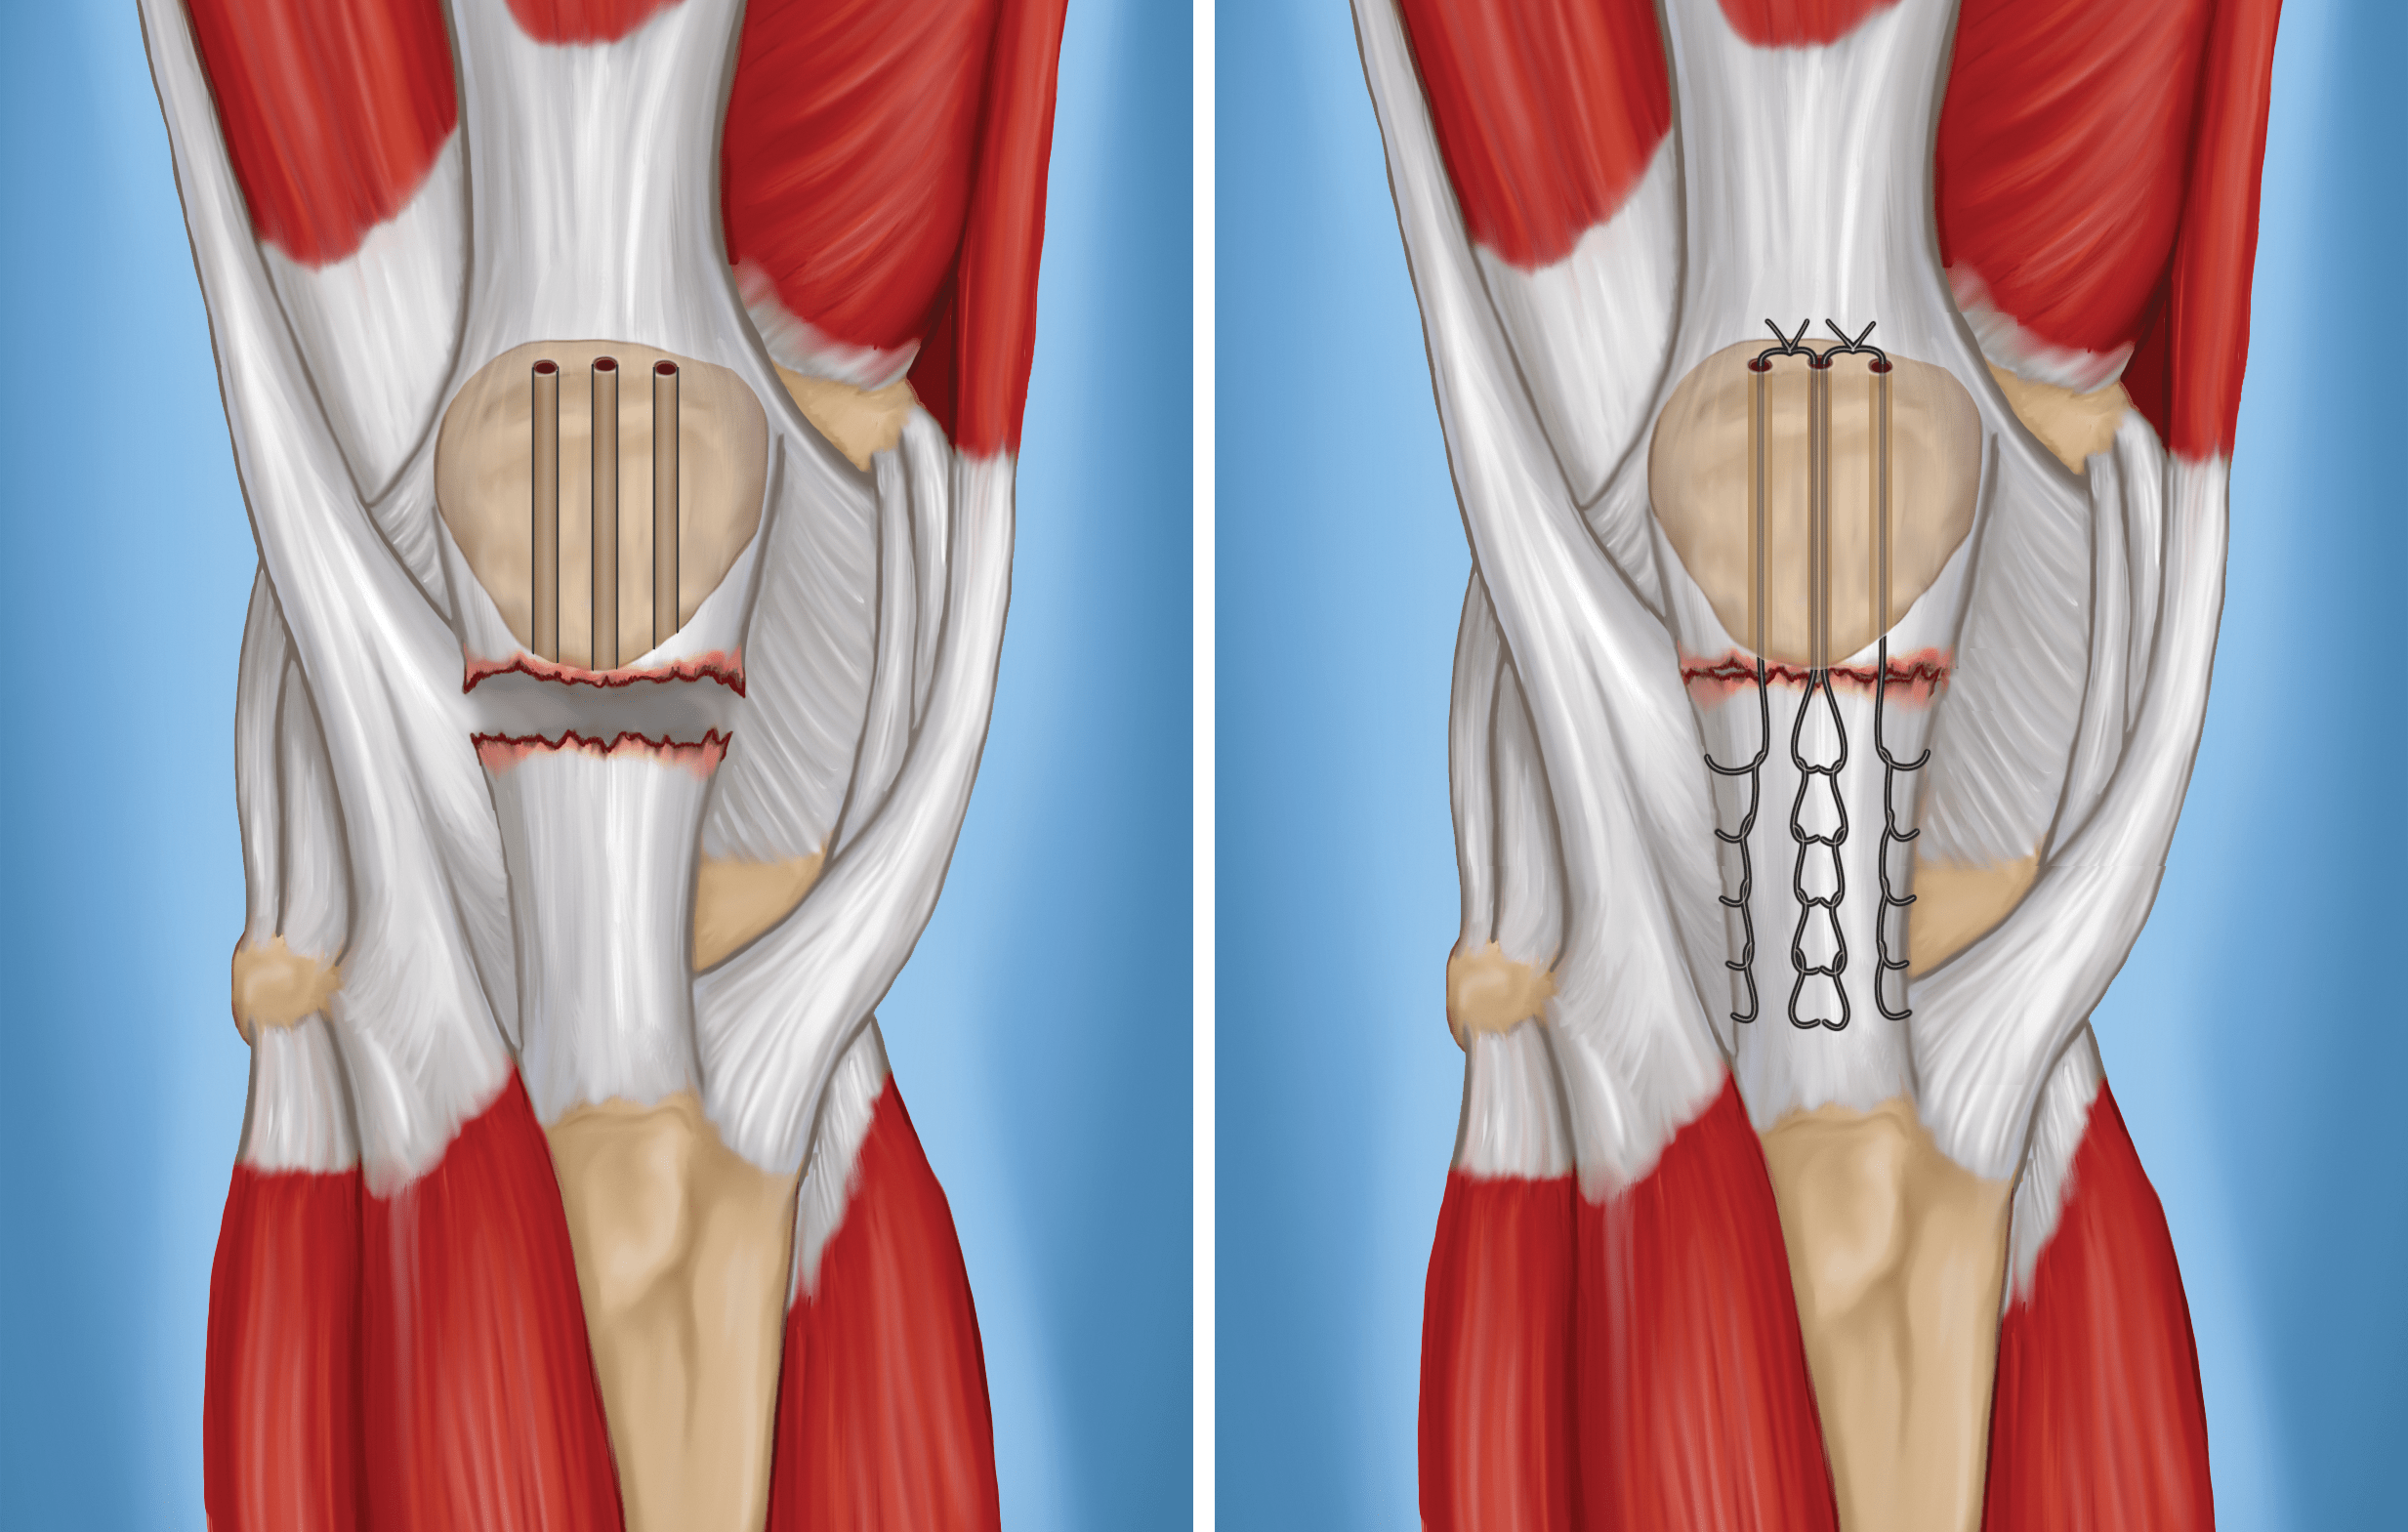

• To reattach the tendon, your surgeon places sutures in the tendon, then threads the sutures through drill holes from the bottom to the top of the kneecap.

• Your surgeon will carefully tie the sutures at the top of the kneecap to get the correct tension in the tendon. This will also ensure that the position of the kneecap closely matches that of your uninjured kneecap.

surgery for patellar tendon tear

To reattach the tendon, the surgeon drills small holes in the kneecap (left) and threads the sutures through the holes to pull the tendon back to the bone (right).

Alternate Technique

Another option in patellar tendon repair is the use of suture anchors. The surgeon attaches the tendon to the bone using small implants called suture anchors. Using these anchors means that the surgeon does not have to drill holes in the kneecap.